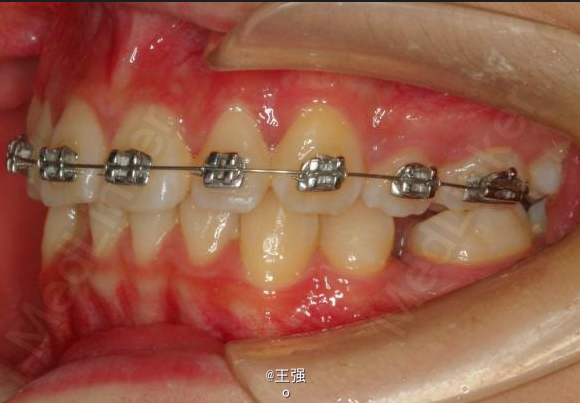

在临床上,我们常常会遇到亚类病例,对于亚类病例,有时需要不对称拔牙,常见的不对称拔牙方法有:上颌对称,下颌数目对称但是位置不对称。还有上颌对称,但是下颌数目不对称。其目的就是为了取得尽可能理想的尖窝对应咬合关系 该病例右侧是中性关系,左侧是中性偏远中关系,上颌中线正,下颌中线左偏约1mm。左侧磨牙关系距离中性关系约差2mm左右。如果采用对称性拔除下颌左右四,我们面临的问题是,一、如何保证矫治后上下中线一致,二、如何保证左侧磨牙关系矫治后为中性关系。治疗过程中势必会用到不对称牵引。我个人认为除非是功能性的因素,矫治过程中最好不要用不对称牵引。 关于中线和磨牙关系的问题,我认为应在矫治计划制定时就应考虑到,而不是等到矫治第三阶段所谓精细调整阶段再来解决。事实上到了这个阶段采用了不对称的牵引,即使暂时取得了中线对齐的矫治目的也是不稳定的。 这个病例,用了不对称的拔牙,右下拔四,左下拔五。下颌牙齿在漂移的过程中(几乎没有外来力量),下前牙自然就会向右比向左多漂移一些,中线在下颌还没有开始矫治时就对齐了,左下六因没有五的存在,自然就向近中多漂移一些,和上颌六形成中性关系。接下来的矫治就会非常简单,而结果自然也非常稳定。